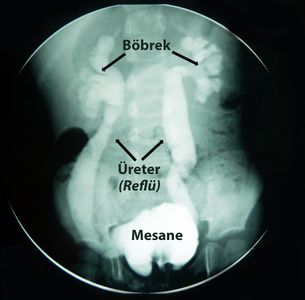

İdrar kesesindeki idrarın yukarı idrar yollarına (böbreğe doğru) kaçmasıdır.

Reflü tanısı için günümüzde kullanılan tanı yöntemleri: